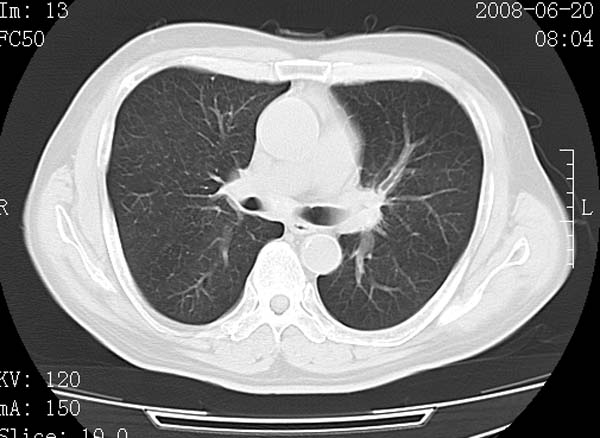

以下是引用守望可可西里在2008-6-24 1:11:00的发言:[br][br] 考虑为周围型肺癌:[br] 1.分叶结节,形态极不规则,蟹足样伸展的恶性浸润特征比较明确。[br] 2.磨玻璃影中由多个更高密度小结节聚集呈梅花瓣样。[br] 3.局部胸膜凹陷征比较明确。[br][br] 另:纵隔胸膜明显增厚、粘连。

以下是引用zjzjr在2008-6-24 11:19:00的发言:[br]支持左下肺周围型肺癌伴右肺转移,纵隔淋巴结转移,心包积液.

以下是引用zhangling在2008-6-24 14:56:00的发言:[br]我们科室意见报告为[br][br]1考虑左下肺周围型肺癌[br]2右肺小结节考虑转移瘤,纵隔淋巴结转移[br]3心包积液. [br] 各位老师分析的相当好 谢意[br]